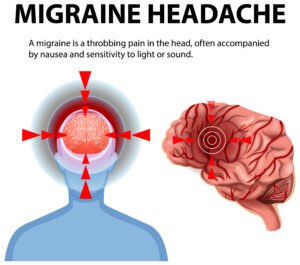

- Headache